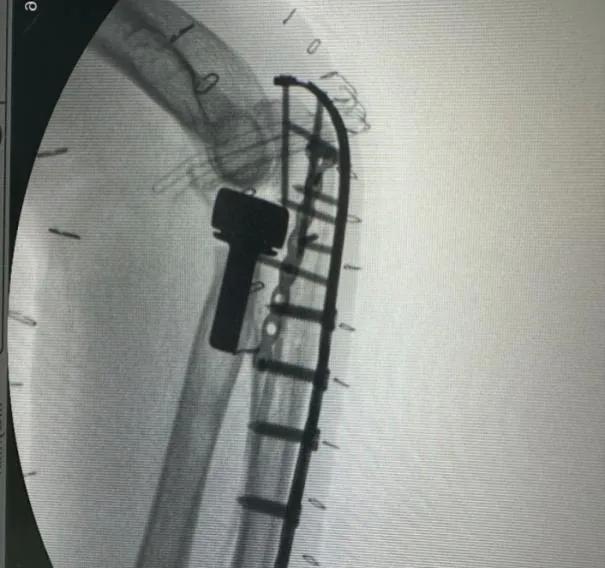

▲左肘關節術前

左肘關節CT平掃+三維檢查提示

左肘關節面對位欠佳

左尺骨鷹嘴及橈骨頭骨折

周圍軟組織腫脹